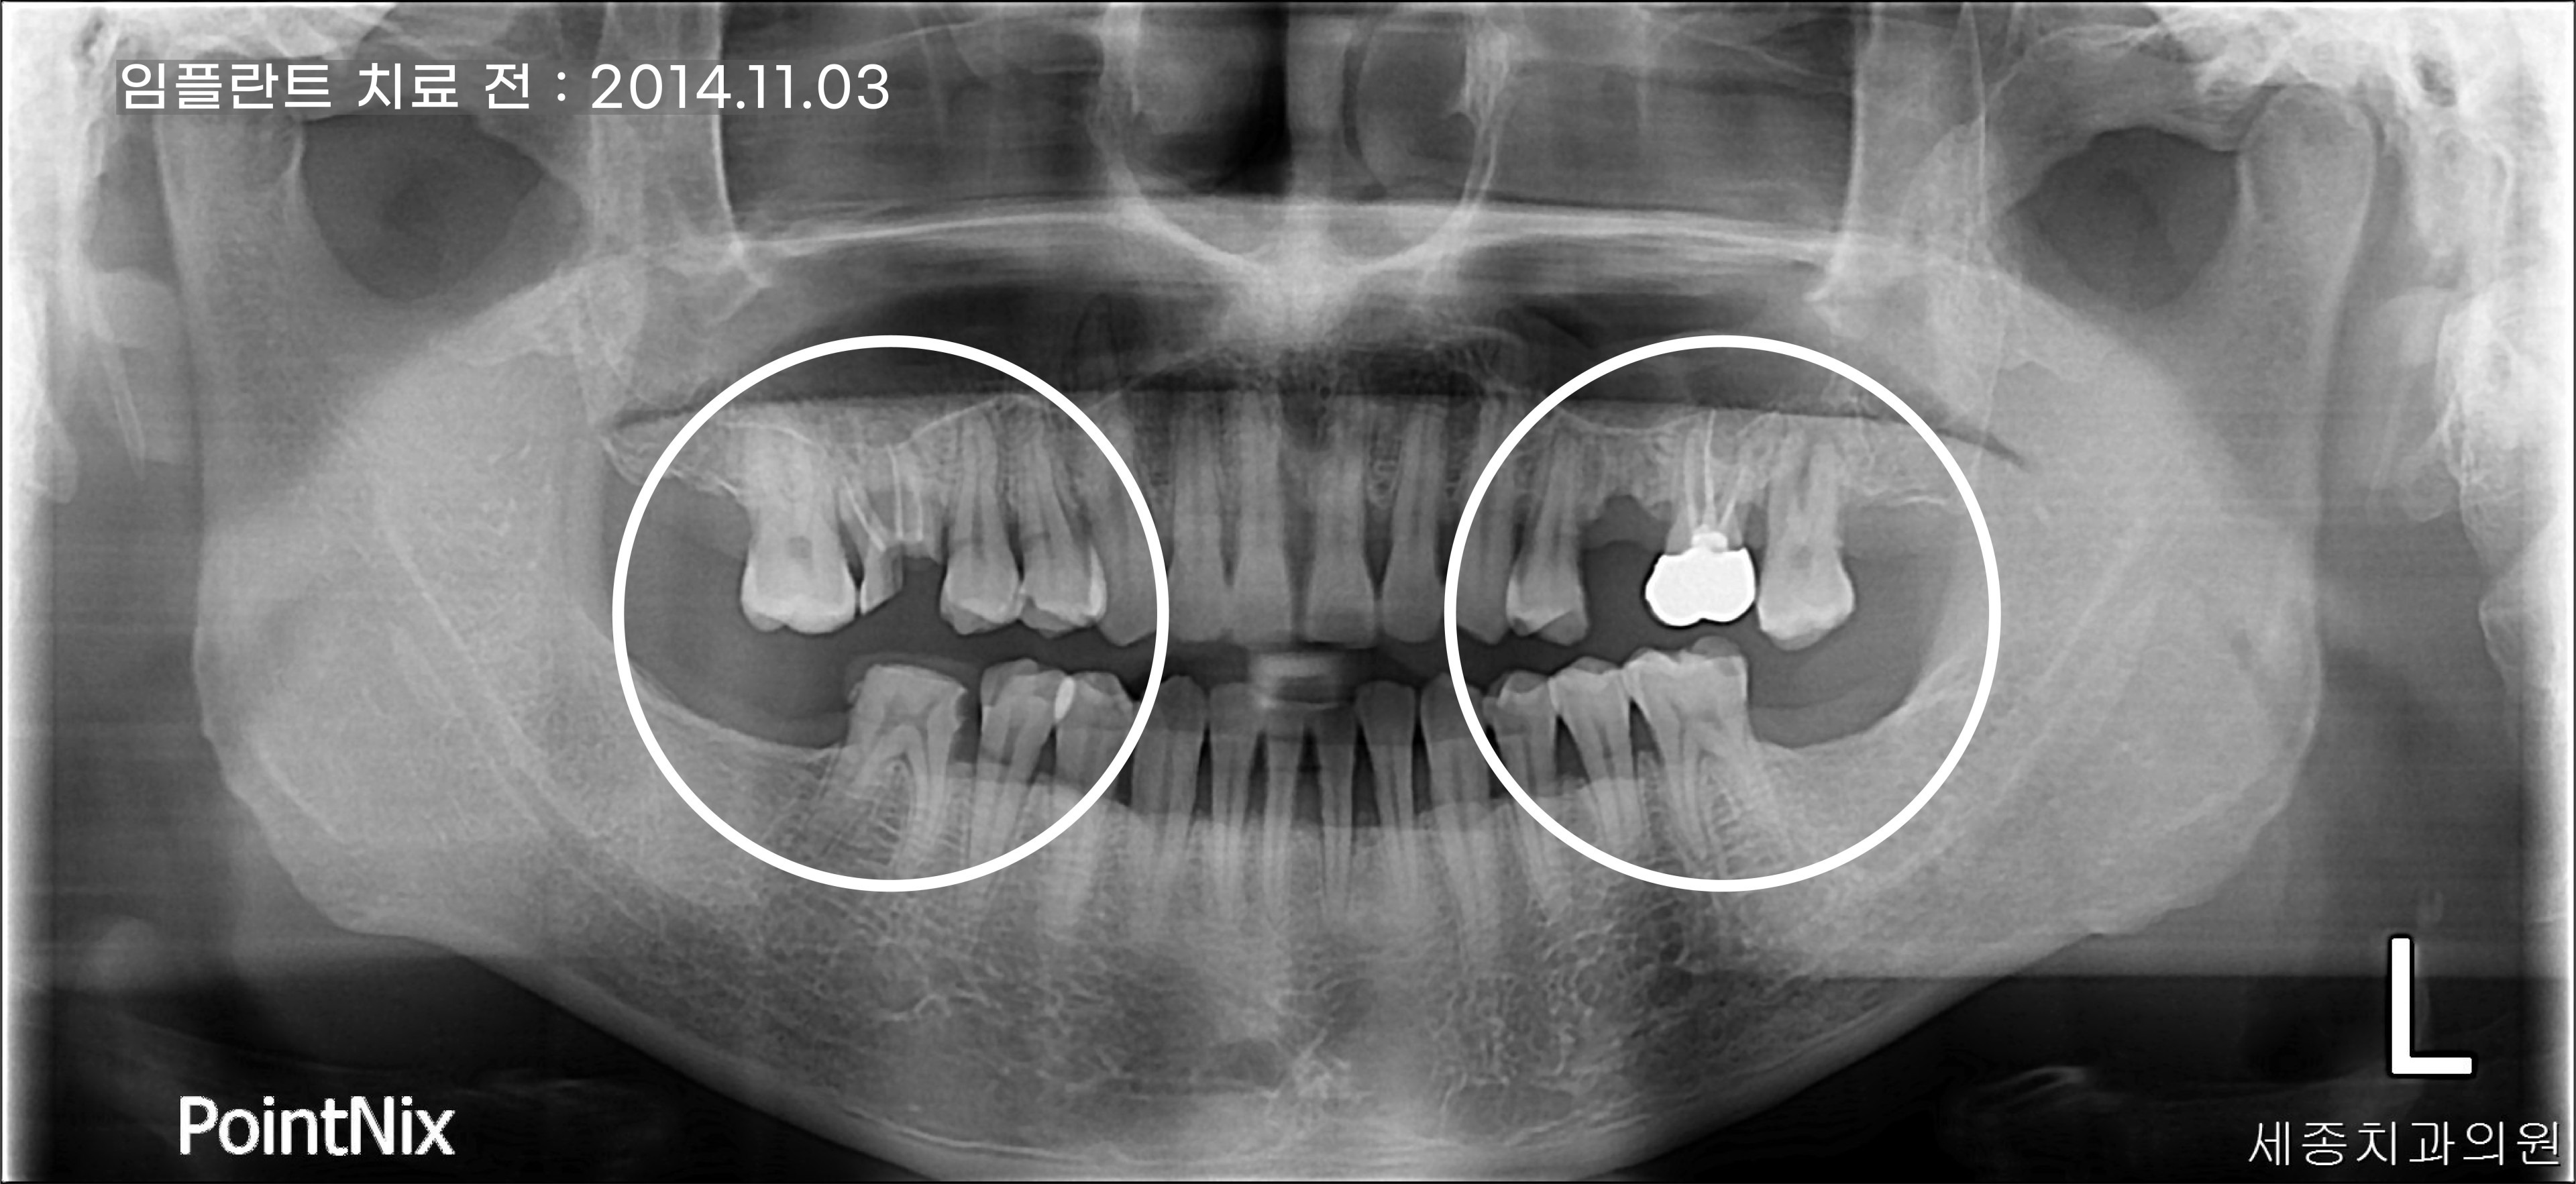

해운대임플란트치과 세종치과 50대 남성 환자의 부러진 치아의 파노라마를 살펴보니 과거에 신경 치료를 한 치아였는데요.

아무래도 하악 어금니가 없어 신경치료를 한 치아로 저작기능을 하다 보니 강한 힘을 버티지 못하고 파절이 된 것 같았습니다.

부러진 치아의 면적이 커서 남아 있는 치아를 살리기에는 치아 기둥이 너무 짧아 살리기 어려운

상태로 판단되어 치아를 발치하고 임플란트를 식립하기로 했습니다.

그 외에 하악의 양쪽 어금니와 상악의 상실된 치아도 임플란트를 식립하여 안정적인 구강 환경을 되찾아

드릴 수 있게 치료 계획을 세우게 되었습니다.

상악의 좌측 어금니는 치아 자체에는 문제가 없어 보이지만 다른 치아에 비해 아래로 쳐진 것을 확인할 수 있는데요.

치아 상실을 오래 방치하게 되면 맞물리는 치아가 없어 치아가 점점 아래로 내려오기 때문에 건강했던

치아마저 임플란트 치료를 할 수밖에 없습니다.